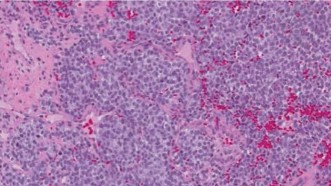

Ewing sarcoma (ES) is a highly aggressive, malignant small round blue cell tumor of bone and soft tissue, belonging to the Ewing sarcoma family of tumors (ESFT). It is characterized by specific chromosomal translocations, most commonly t(11;22)(q24;q12), resulting in the EWS-FLI1 fusion gene, which serves as a molecular hallmark and drives its oncogenesis.

- Histopathological examination, including immunohistochemistry (CD99, NKX2.2) and molecular genetics (EWS-FLI1 fusion), confirms diagnosis and assesses tumor response to neoadjuvant chemotherapy (tumor necrosis percentage), which is a key prognostic indicator.